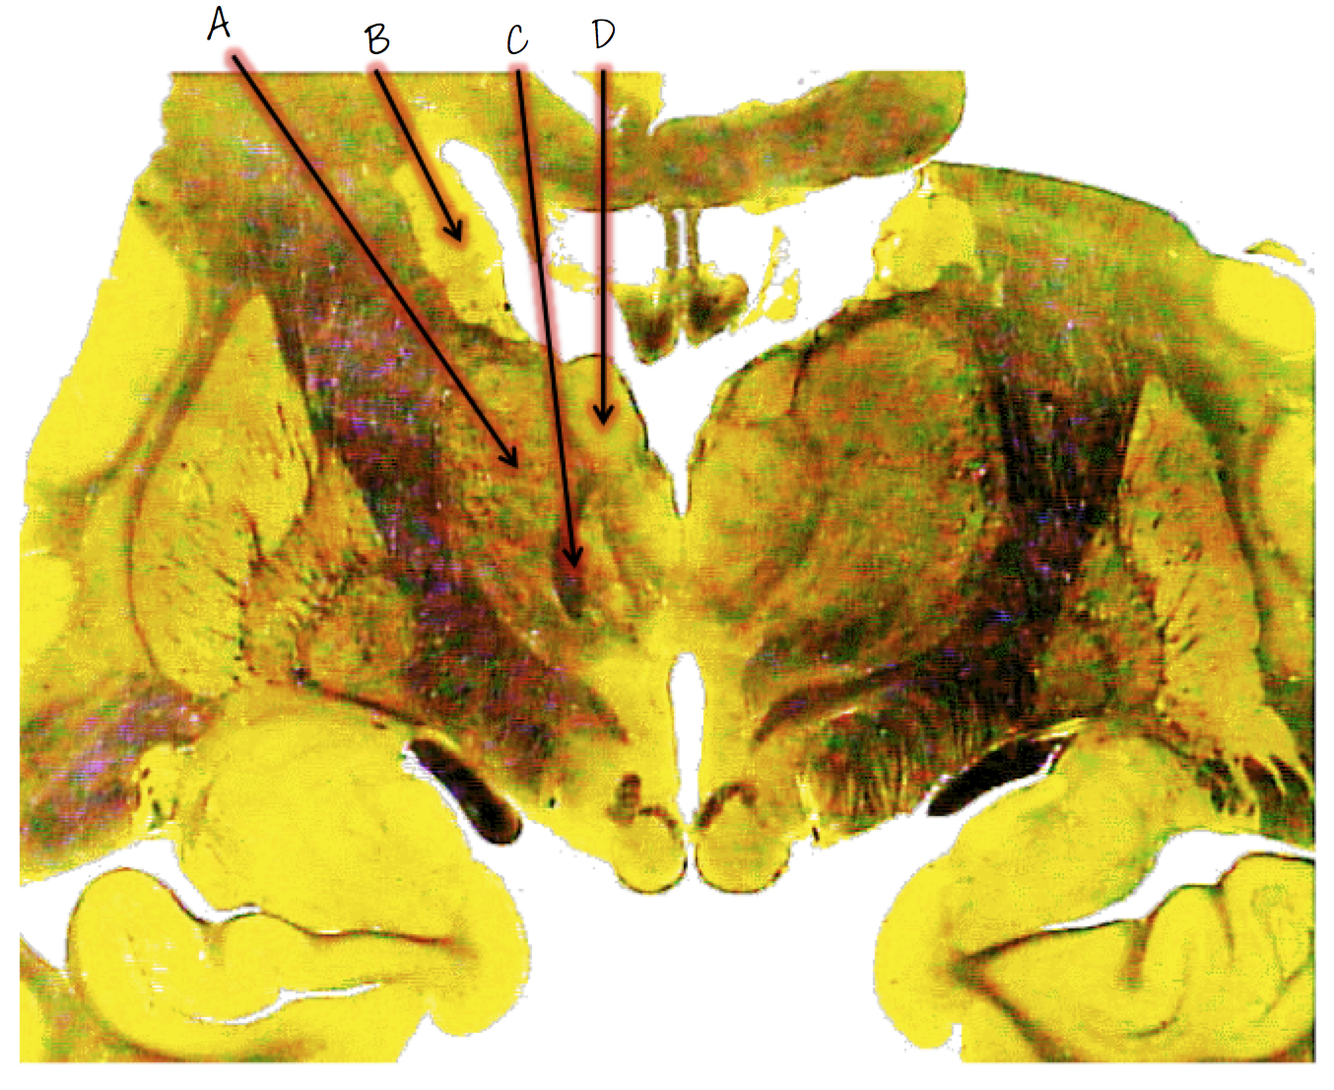

A: caudate nucleus

B; anterior nucleus of thalamus

C; mammillothalamic tract

D; globus pallidus

E; putamen